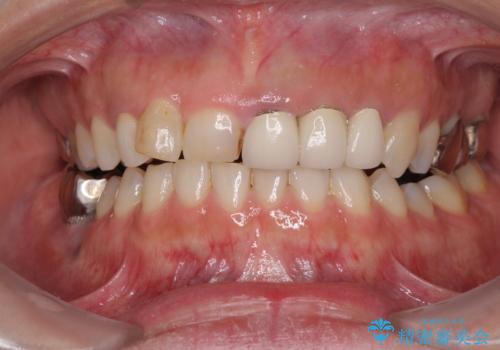

[ 前歯開咬 ] 前歯が噛んでいない マウスピース矯正治療

担当医 大元洋佑

![[ 前歯開咬 ] 前歯が噛んでいない マウスピース矯正治療の症例 治療前](https://seimitsushinbi.jp/wp/wp-content/uploads/2022/11/IMG_4669-500x350.jpg?v=1668218426)